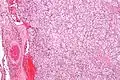

Micrograph of a carotid body tumor (a type of paraganglioma). | |

On microscopic inspection, the tumor cells are readily recognized. Individual tumor cells are polygonal to oval and are arranged in distinctive cell balls, called Zellballen.[8] These cell balls are separated by fibrovascular stroma and surrounded by sustentacular cells.

By light microscopy, the differential diagnosis includes related neuroendocrine tumors, such as carcinoid tumor, neuroendocrine carcinoma, and medullary carcinoma of the thyroid.

With immunohistochemistry, the chief cells located in the cell balls are positive for chromogranin, synaptophysin, neuron specific enolase, serotonin, neurofilament and Neural cell adhesion molecule; they are S-100 protein negative. The sustentacular cells are S-100 positive and focally positive for glial fibrillary acidic protein. By histochemistry, the paraganglioma cells are argyrophilic, periodic acid Schiff negative, mucicarmine negative, and argentaffin negative.